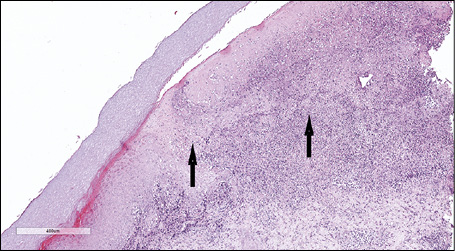

At scanning magnification, the histopathology showed a broad dermo-epidermal ulceration with an underlying purulent base (Figure 2). At higher magnification, the epidermis was characterized by necrotic keratinocytes with pycnotic nuclei and dense eosinophilic cytoplasm (Figure 3, arrowhead) and by scattered keratinocytes with a “shadow cell” appearance (enlarged cells with eosinophilic cytoplasm without well-defined nuclei [Figure 3, arrow]); suppurative changes were detected within the papillary dermis with marked neutrophilic exocytosis (Figure 3, asterisk). Some keratinocytes showed ballooning degeneration (Figure 4, arrow). An interstitial and perivascular/peri-adnexal inflammatory infiltrate composed of neutrophils and lymphocytes was observed in the deep dermis, associated with endothelial swelling (Figure 5, arrowhead) without fibrinoid necrosis of the vascular wall.

Figure 2 - Haematoxylin and eosin (H&E) stain. At scanning magnification (10x) the histopathology showed a broad dermo-epidermal ulceration with an underlying purulent base (arrows).